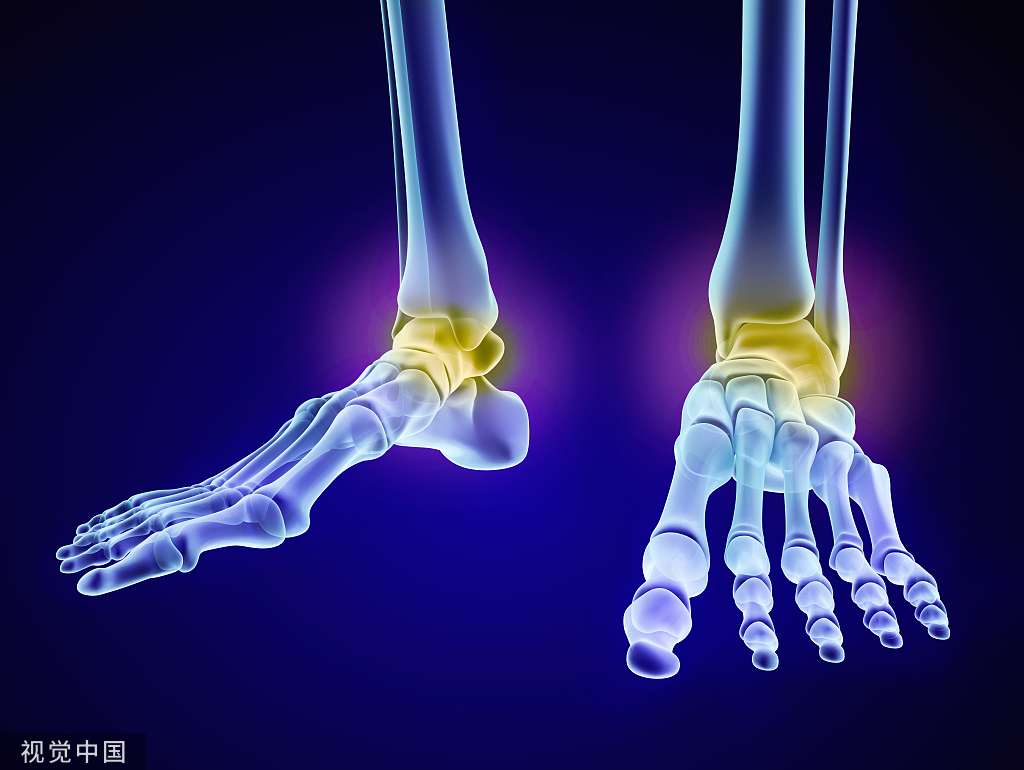

1、胫骨内踝骨骺:胫骨内踝的骨骺有多个骨化中心并非少见,特点是边缘光整,骨皮质连续,不确定时可做双侧对比。

不确定时可做双侧对比

18、跟骨骨骺:为跟骨后缘骨化中心,可为多发的骨化中心。